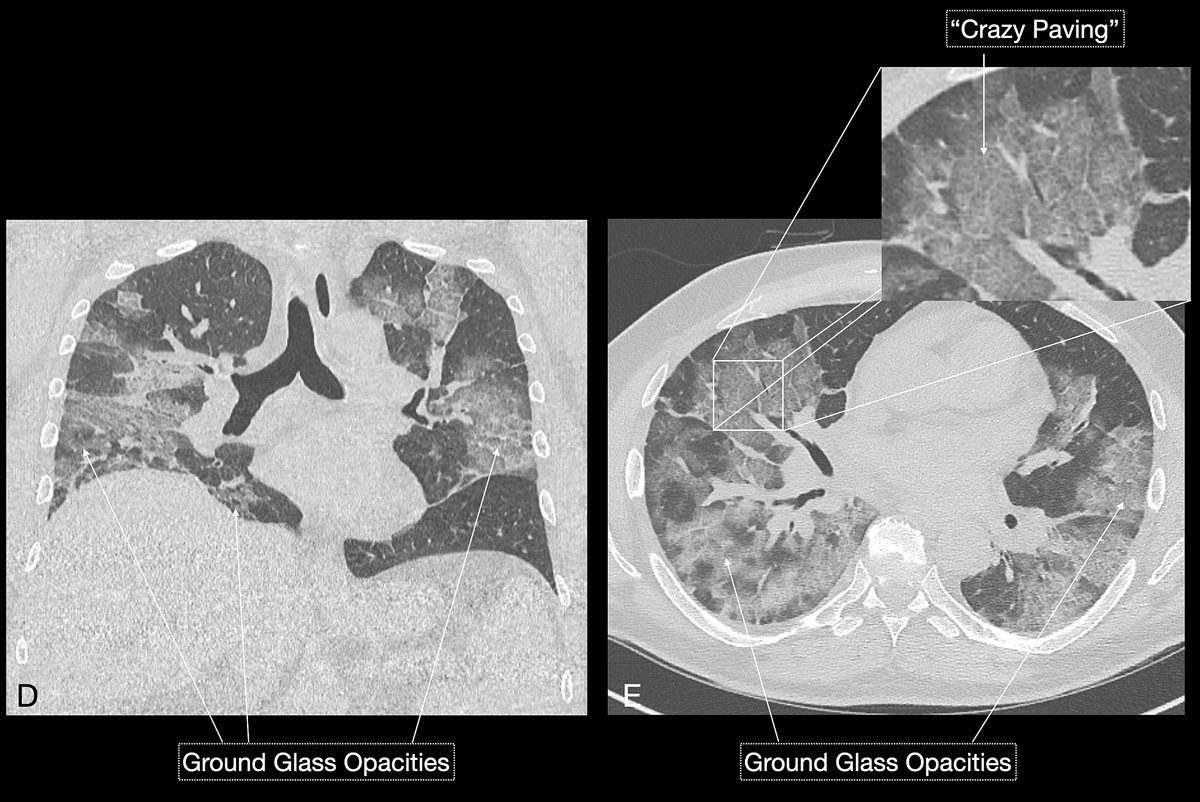

Imaging features in our patient cohort are summarised in table 2 and compared with manifestations observed on CT in Chinese patients [20]. Classic imaging findings are bilateral ground glass opacities with or without areas of consolidation, predominantly with a peripheral or basal lower lobe distribution (figs 3 and 5 ). Unilateral or bilateral ground glass opacities – the hallmark of an early infection (0–4 days) – were observed in almost all COVID-19 patients on chest CT examinations (97% positivity). Given the very subtle appearance of ground glass opacities, their detection on chest x-ray is difficult and often not made prospectively. The second most apparent imaging patterns are consolidations, which are typically multifocal, subpleural/peripheral, or in a peribronchovascular distribution (figs 3 and 5 ). As the disease progresses (5–8 days), the extent of ground glass opacities increases and the amount of consolidation rises (fig. 6). The ground glass opacities progressively transform into consolidative opacities featuring patterns of organising pneumonia of varying extents in the peak stage (10–13 days), before gradually resolving with the patient’s recovery. Typical patterns of organising pneumonia include subpleural lines/bands, perilobular thickening, arcade and atoll signs. Generally, the development of consolidations is a sign of disease progression and is more common in patients above 50 years old and those who have experienced a longer duration of symptoms.

Figure 6 DE Over time the patient’s dyspnoea increased and the subsequent chest CT scan (D, E) confirmed worsening disease with increasing ground glass opacities and an apparent “crazy paving” pattern, the latter suggesting a progressive stage of disease.

Reticular opacities are also often seen with COVID-19 patients and likely represent lymphocytic interstitial infiltration, similar to other viral infections (fig. 6). A unique CT pattern with a thickened intra- and interlobular interstitium superimposed on background ground glass opacity was observed in 5–36% of COVID-19 patients. The CT pattern had a specific appearance of “crazy paving”, since it resembles a mosaic of irregular paving stones (figs 6 and 7 ). This sign likely represents the combination of alveolar oedema and interstitial inflammatory changes in the setting of diffuse alveolar damage and is most commonly seen in the progressive stage of the disease [22, 23].